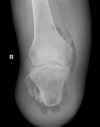

Unusual appearance of air in soft tissue on ultrasound